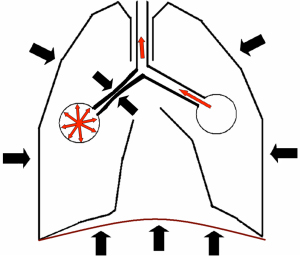

PEEP (PEEP - pozitív kilégzési nyomás) dolgozta ki, hogy megakadályozza EZDP (kilégzési légúti lezárás) angol Air csapdázási (szó - levegő csapda).

COPD (krónikus obstruktív tüdőbetegség, vagy a COPD - krónikus obstruktív tüdőbetegség, hörgő belsejébe csökkentjük nyálkahártya ödéma, amikor a kilégzési izomerő légzőszervi izmok keresztül tüdőszövet továbbítják a külső fal a hörgők, tovább csökkentve annak lumen rész hörgőcskék .. nélkül porcos váz félkörök, nem szorított teljesen kilélegzett levegőt, és zárva a tüdőben, mint a csapda (bekövetkezik Air csapdázási) hatások - .. és a gázcserét rendellenességek hiperextenziós (hiperinfláció) alveolusok.

Azt is megfigyelték, hogy az indiai jóga és más légúti terapeuták a betegek kezelésére asztma széles körben elterjedt lassú kilégzés ellenállás (pl hangadás, ha kilégzés beteg énekel „és-és-és-és” vagy „oo-oo-oo y”, illetve exhales át a csövön, csökkentette a vízbe). A nyomás tehát a létrehozott belsejében bronchiolusokat alátámasztó azok átjárhatóságát. A modern lélegeztető PEEP által létrehozott ellenőrzött vagy felügyelt Kilégzőszeleppel.